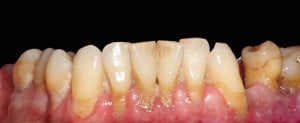

Pacjent lat 60, duże recesje dziąseł, niewyedukowany w zakresie prawidłowej higieny jamy ustnej. Został skierowany na higienizację profesjonalną przez lekarza prowadzącego. Na pierwszej wizycie siekacze dolne pacjenta wyglądały tak: zdjęcie 1, zdjęcie 4.

Widać wyraźnie, że kamień i gruba warstwa płytki bakteryjnej wywołał stan zapalny dziąseł – są przekrwione, i opuchnięte. Higienistka wykonała skaling naddziąsłowy skalerem EMS, wypiaskowała zęby piaskiem Air-Flow Plus oraz wypolerowała pasta polerską. Po zabiegu różnica wyglądzie zębów jest diametralna: zdjęcie 2, zdjęcie 5.